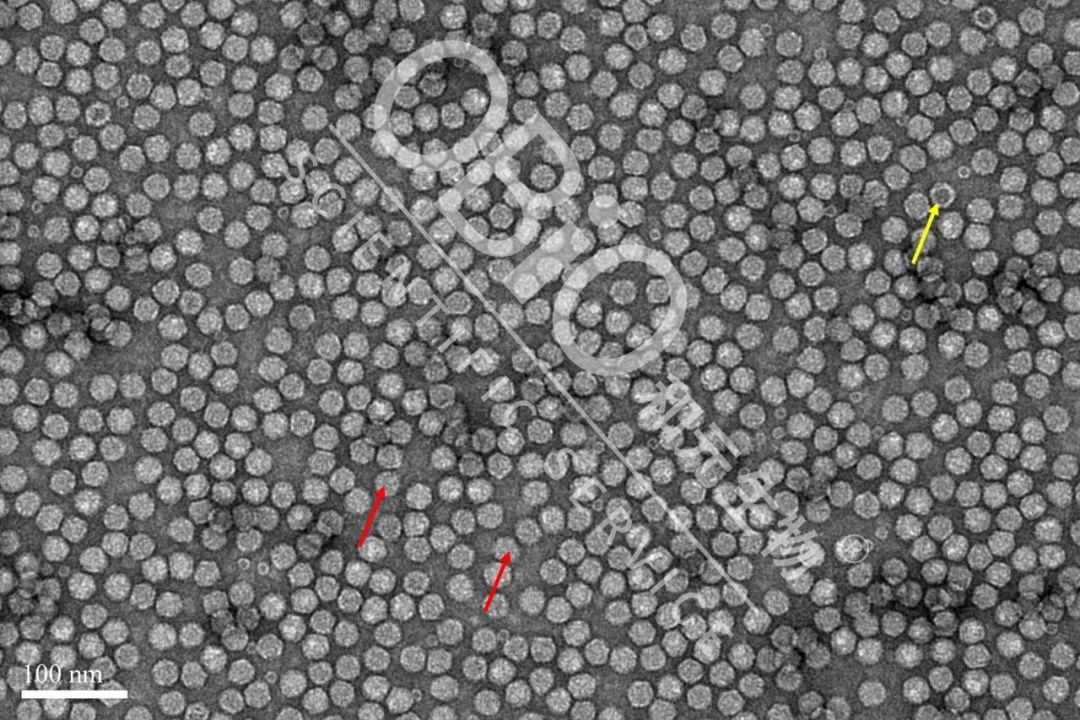

图2 rAAV载体生产空壳率大比拼

为了更好地显示米乐生物AAV产品的属性,我们选取大视野进行比较

图3 米乐生物rAAV载体生产空壳率

电镜结果:包装DNA基因组的病毒颗粒为实心颗粒(红色箭头);空病毒颗粒中间存在空洞(黄色箭头)